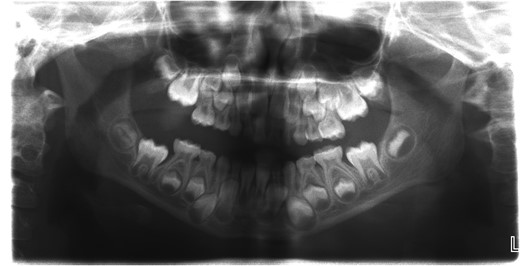

A 6-year-old girl presented to the Emergency Department with a suspected mandibular dislocation after falling off her scooter. She was previously fit and well with no significant medical history. She had complete restriction of all mandibular movements and trismus. The dental occlusion demonstrated a cross-bite with all the posterior teeth in contact and a mandibular asymmetry with the chin significantly deviated to the left side. Radiographic investigations (orthopantomogram (OPG) and postero-anterior (PA) mandible images) were performed but confirmation of the dislocation could not be determined on these views (Fig. 1). Consequently, a computerized tomography (CT) scan was performed that confirmed significant displacement of the condyle anteriorly and superiorly into the infratemporal fossa (Fig. 2). In addition calcification of the lateral and medial pterygoid muscles was noted on the affected side indicating chronic nature of the condition. Discussion with the patient’s general dental practitioner (GDP) revealed that the patient had a pre-existing dental malocclusion comprising of a cross-bite and mandibular asymmetry and this was also corroborated by a photograph taken well before the scooter accident. On this evidence it was therefore presumed that the condyle had been dislocated for many months or years and the scooter accident had only highlighted this. There were no other traumatic events of note in the history. The TMJ could not be convincingly reduced via a Hippocratic manoeuvre under a short general anaesthetic despite several attempts. In order to re-image the TMJ a magnetic resonance imaging scan was performed to prevent additional irradiation. This scan confirmed that the TMJ was still dislocated and had not been reduced. Due to the unsuccessful closed reduction, it was decided to perform an open reduction via a Risdon incision. When reduction with traction wires at the mandibular angle failed a bone hook was placed into the sigmoid notch and the dislocation was reduced using a fair degree of force.

Computerized tomography (CT) scan of the dislocated left temporomandibular joint.